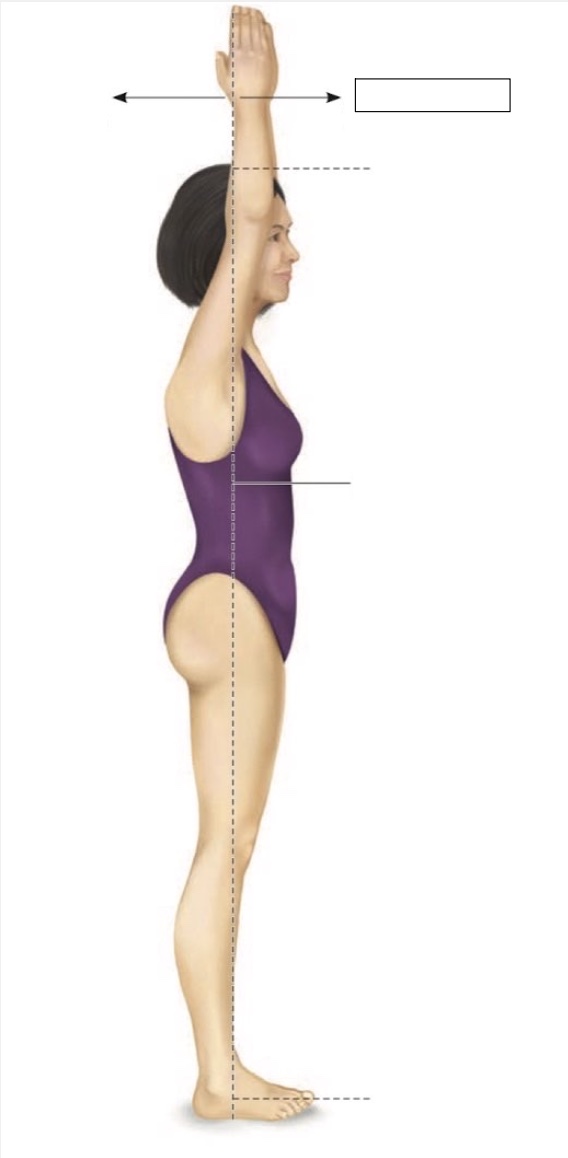

Superior

Midline

Midaxillary

Torso